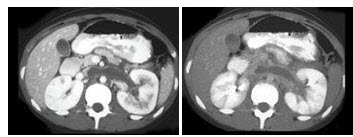

男,56岁,无规律上腹痛,左锁骨上淋巴结肿大,消瘦、乏力,影像检查如图,最可能的诊断是()

A.腹膜结核

B.胃溃疡穿孔

C.胃癌并盆腔种植

D.胃及腹腔淋巴瘤

E.肠系膜淋巴管瘤

96、单项选择题 男,65岁,右侧肢体肌力弱,CT示左额顶叶有-2.5cm×4cm混杂密度区,花环样强化,中线右移,最大可能为()